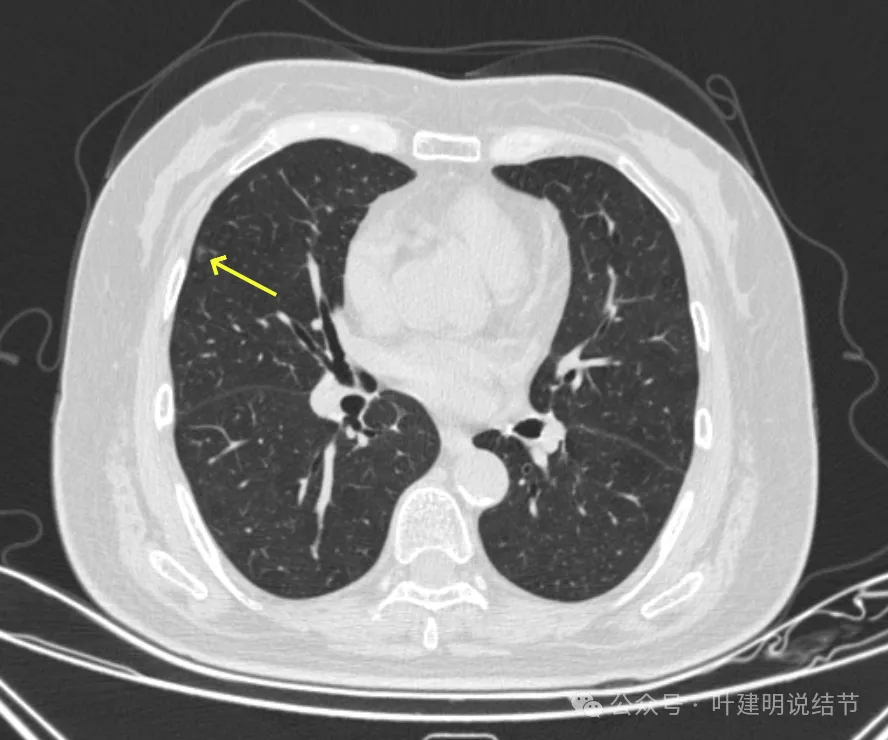

病灶7-9:右肺上叶淡磨玻璃结节,轮廓较清。

病灶32:上叶尖后段胸膜下此灶密度较高,有小血管进入,但病灶本身还小,考虑原位癌可能性稍大。

病灶33:右上叶磨玻璃结节,考虑不典型增生或原位癌可能性较大,总体风险仍低。

你的两肺我数了一下,较明显的多达48处结节,还有过小的或不太确切是结节的不算,但估计在随访中仍会是结节的。大部分都是淡磨玻璃结节,轮廓与边界较为清楚,没有显著实性成分。其中最大最主要的病灶是左上叶胸膜下的,此灶轮廓清楚,磨玻璃密度,贴着胸膜,灶内密度稍不均,但未见明显异常增粗的血管进入穿行,胸膜牵拉也不厉害,考虑仍是微浸润性腺癌或浸润性腺癌贴壁为主型的阶段,近期风险仍不大,何况两肺这么多病灶,即使切了主病灶也不能解决后续其他结节进展的问题。所以个人仍倾向在风险相对可控不大的情况下,继续随访。6-9个月复查应该是安全的,其实12个月复查也不见得就会有风险。待关注最主要的病灶有风险了,再来综合评估考虑干预事宜,包括如何干预,以及处理哪几处同侧病灶。意见供参考!